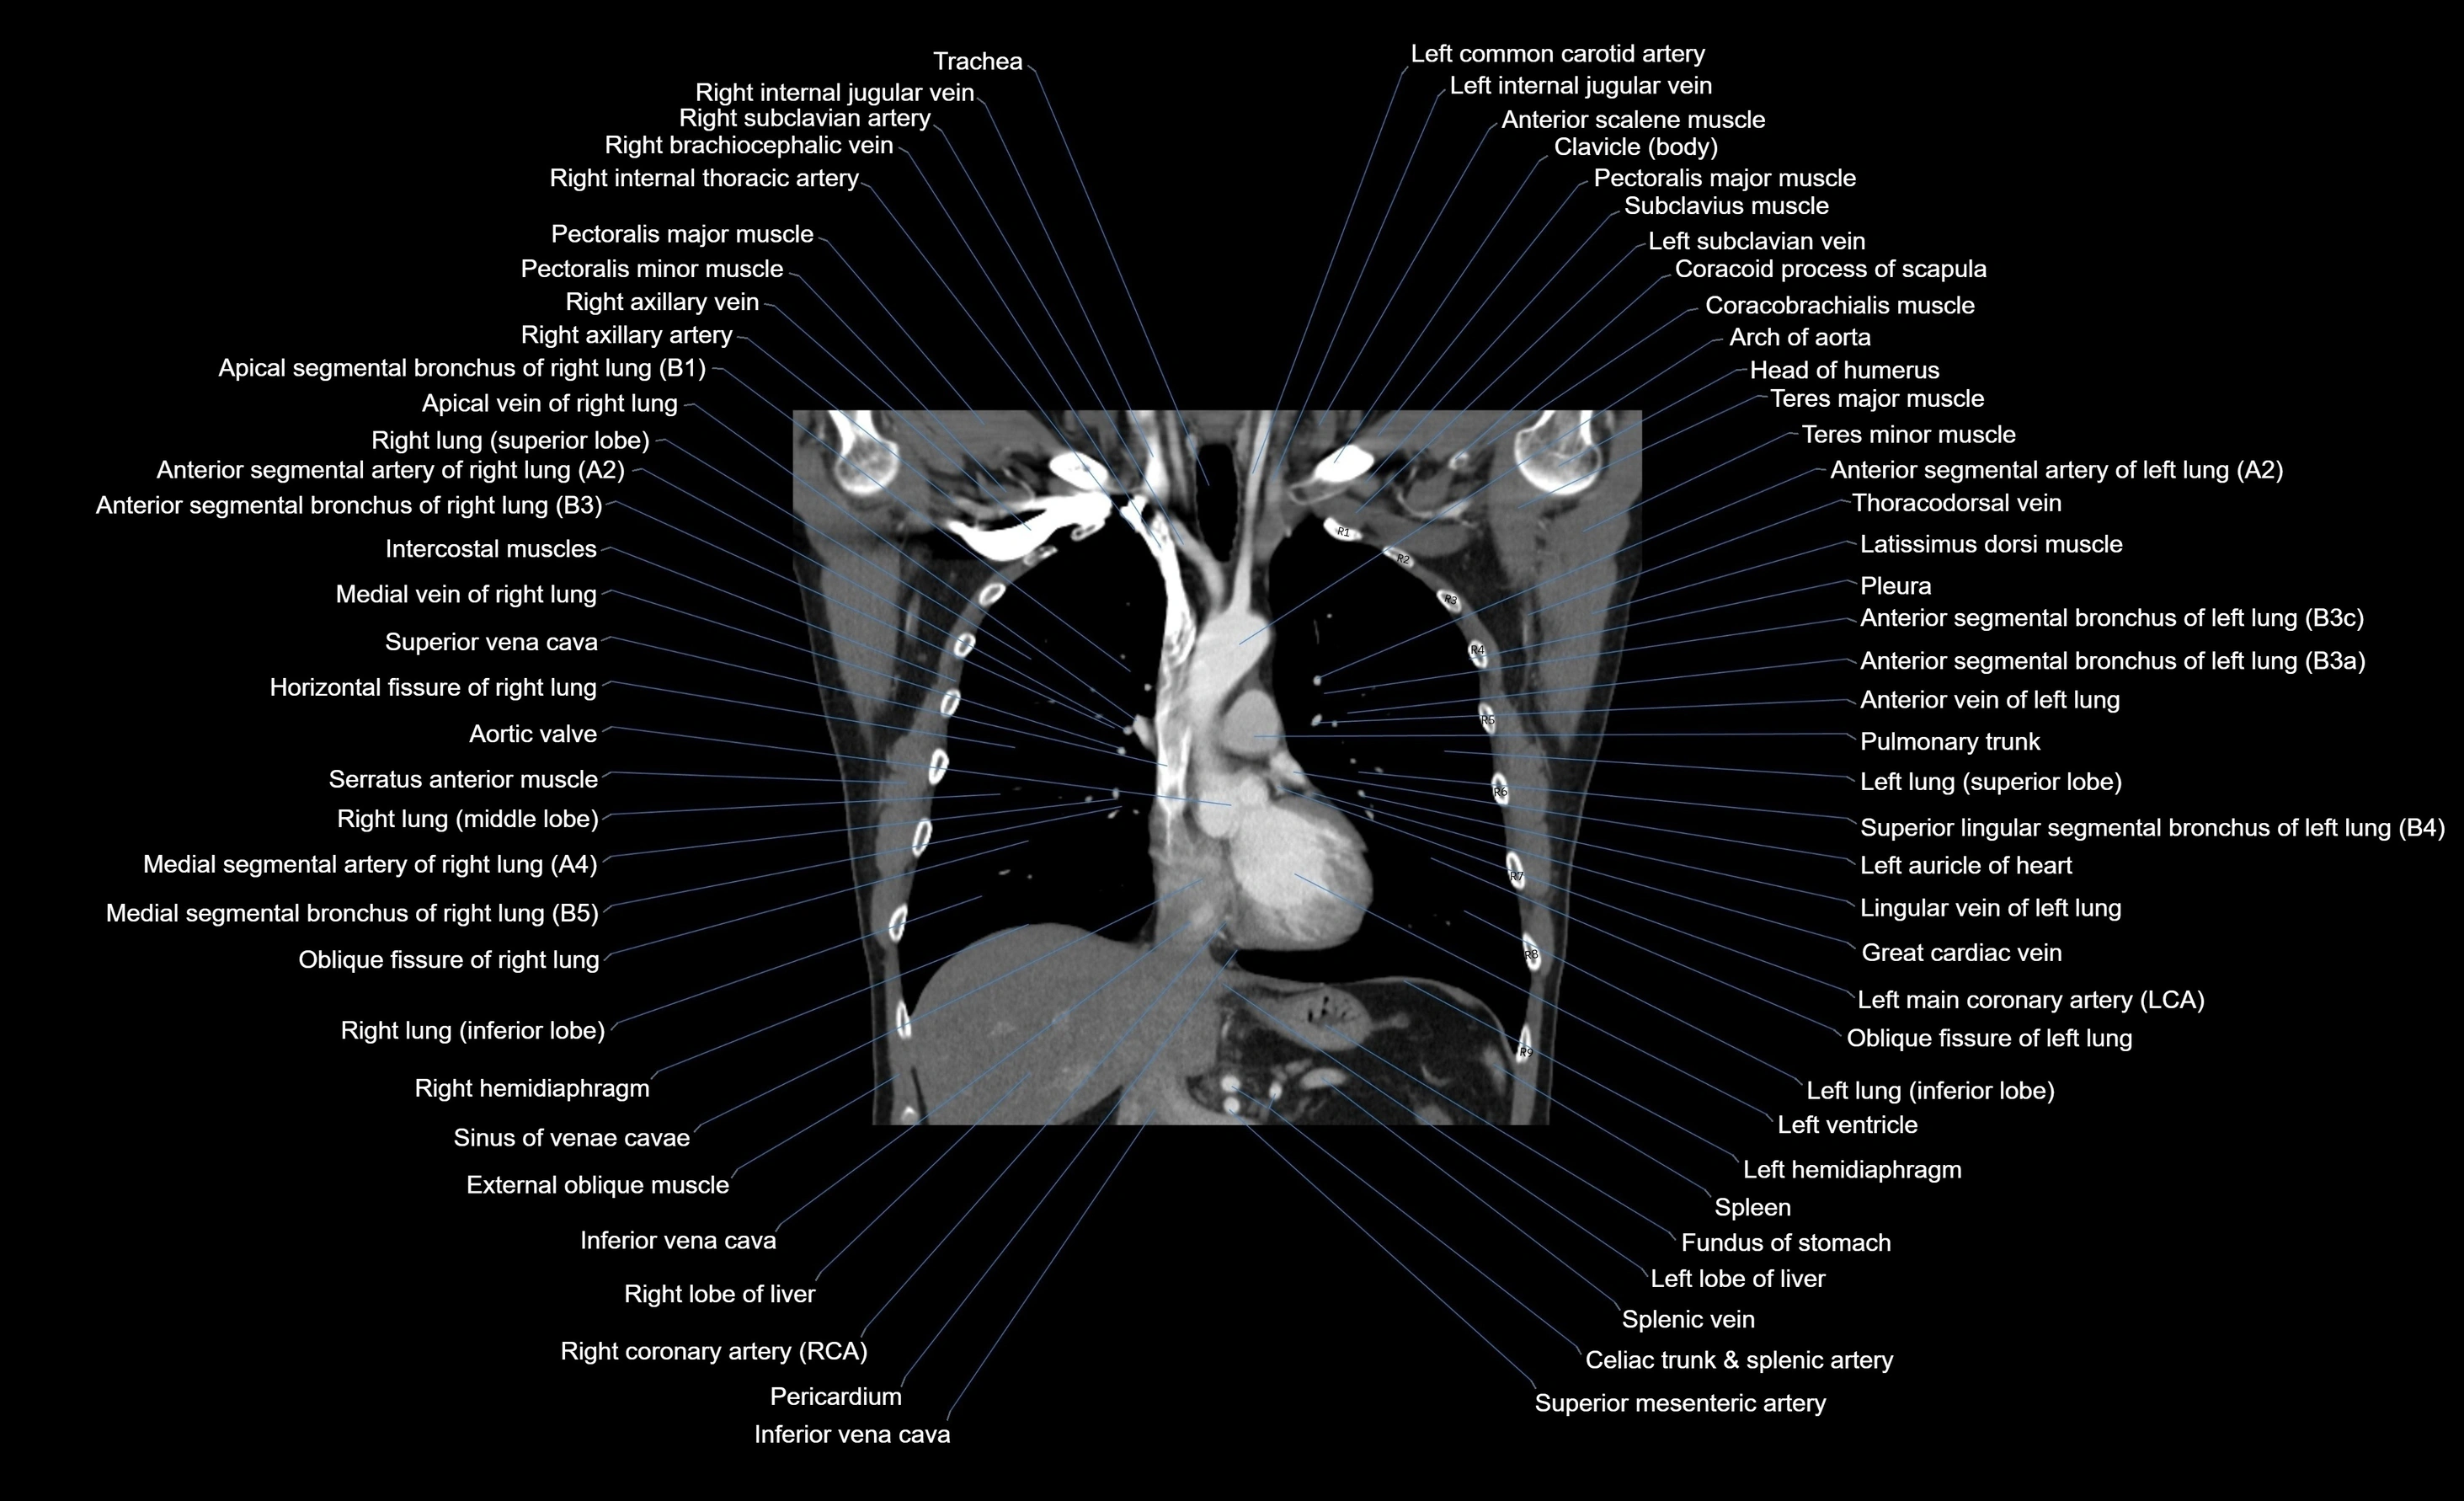

- Aortic valve

- Arch of aorta

- Coracobrachialis muscle

- Coracoid process of scapula

- Costal cartilages

- External oblique muscle

- Great cardiac vein

- Horizontal fissure of right lung

- Inferior lobe of right lung

- Inferior vena cava

- Intercostal muscles

- Latissimus dorsi muscle

- Left Lung (Superior Lobe)

- Left common carotid artery

- Left hemidiaphragm

- Left lobe of liver

- Left lung (inferior lobe)

- Left main coronary artery (LMCA)

- Left ventricle

- Lingular vein of left lung

- Middle lobe of right lung

- Oblique fissure of left lung

- Oblique fissure of right lung

- Pectoralis major muscle

- Pectoralis minor muscle

- Pleura

- Pulmonary trunk

- Right coronary artery (RCA)

- Right hemidiaphragm

- Right lobe of liver

- Right lung (inferior lobe)

- Right lung (middle lobe)

- Right lung (superior lobe)

- Spleen

- Splenic vein

- Superior mesenteric artery (SMA)

- Superior vena cava

- Thoracodorsal vein